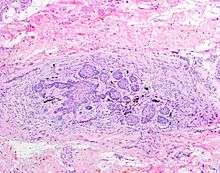

![]() The juxtaoral organ of Chievitz is composed of nests of benign squamoid epithelium closely associated with multiple nerve bundles. The deep location and squamous appearance can histologically mimic invasive squamous cell carcinoma. (Hematoxylin and Eosin stained section, 100x magnification) | |

The Juxtaoral organ in humans is a small longish structure (10–14 mm in length, 1–2 mm in diameter), situated laterally of the buccal muscle in both cheeks. The organ consists of a central ramified cord of an epithelial parenchyma, embedded in connective tissue particularly rich in nerve fibers and sensory receptors. Close relations exist between epthelial cells and nerve endings. Histochemically, the parenchyma displays a characteristic pattern of various enzymes. Sporadically, epithelial follicles containing colloidal material can be found. The organ is surrounded by a dense, perineurium-like connective tissue.